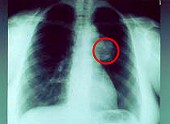

tiene cáncer (aquí un cáncer de pulmón)

y después de todo fue un médico con un diagnóstico que el papá tiene cáncer (aquí un cáncer de pulmón)

Todo el poder generado por su relación salió a la luz sólo en 1964. El médico le dijo a papá que tenía cáncer y calculó que, como máximo, le quedaban de seis meses a un año de vida.

-- foto radiográfica de cáncer de pulmón: http://www.krebsgesellschaft.de/pat_ka_lungenkrebs_diagnose.html?markierung=bronchial